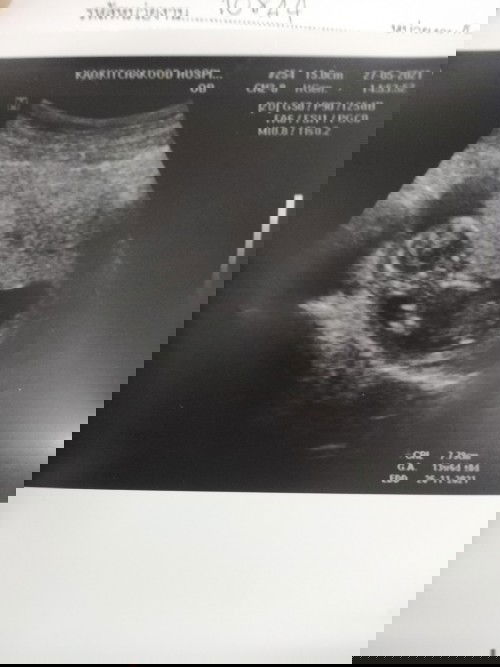

ถ้าความยาวปกติค่ะ น้ำหนักน้องเท่าไหร่คะ